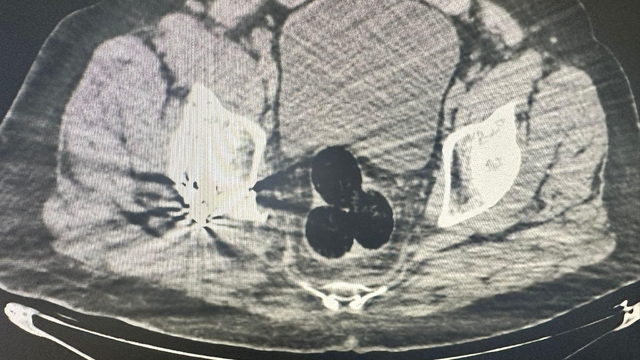

IĞDIR'da, İran'dan yurda giren kişinin hastanede yapılan radyolojik görüntülemede İran uyruklu şüphelinin makatında uyuşturucu tespit edildi. Şüpheli ile onunla bağlantılı olduğu tespit edilen 2 kişi tutuklandı.

Iğdır Emniyet Müdürlüğü Narkotik Suçlarla Mücadele Şube Müdürlüğü ekipleri tarafından, İran'dan ülkeye giren bir kişi, şüphe üzerine hastaneye götürüldü. Burada yapılan radyolojik görüntülemede şüphelinin makatında 3 parça halinde yabancı cisim tespit edildi. Hastanedeki operasyonla çıkarılan 3 pakette 130 gram metamfetamin ele geçirildi. Şüpheli gözaltına alınırken, soruşturma kapsamında polis, bu kişiyle bağlantılı olduğu ve aldıkları uyuşturucuyu kentte kullanıcılara sattığı tespit edilen 2 şüpheliyi daha yakaladı. 47 gram daha metamfetamin ele geçirildi.